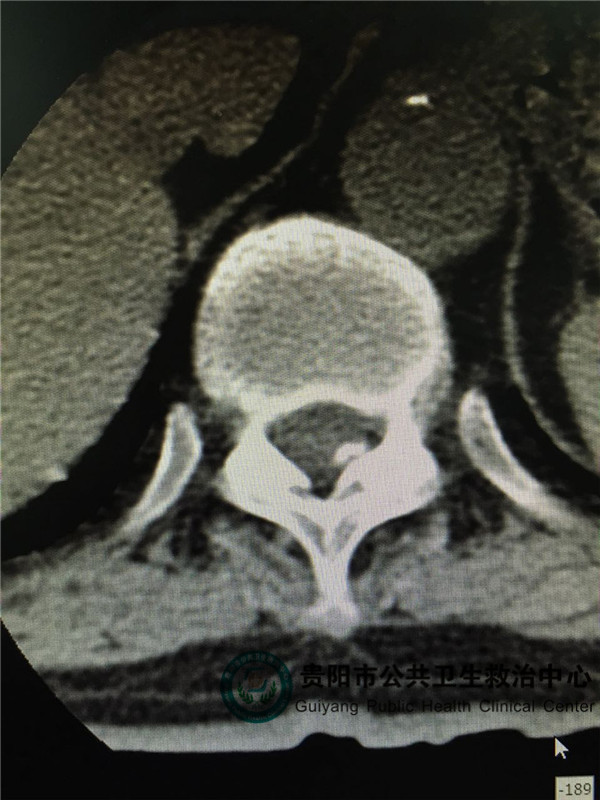

圖2

圖2,圖3,圖4是胸椎病灶節(jié)段CT平掃,可見(jiàn)椎管左側(cè)有占位壓迫脊髓,椎管明顯變窄。和患者體征相符。